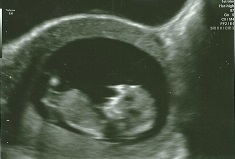

Today I had my second scan. I'm exactly 12 weeks pregnant. I have a 2 pictures from today and 1 picture from the last week (11 weeks pregnant). Please could you guess gender of my baby? MANY THANKS!!! Lucy